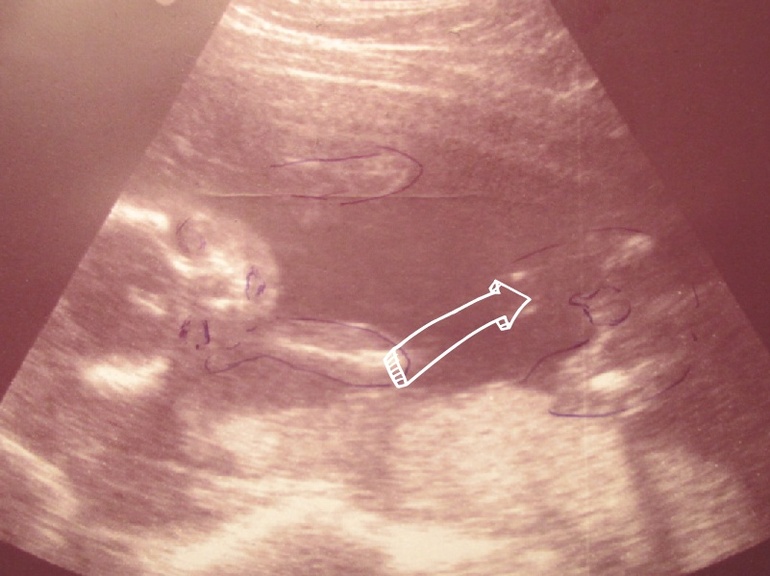

Особенности УЗИ при определении пола ребенка

Раздел: Идеи и советы